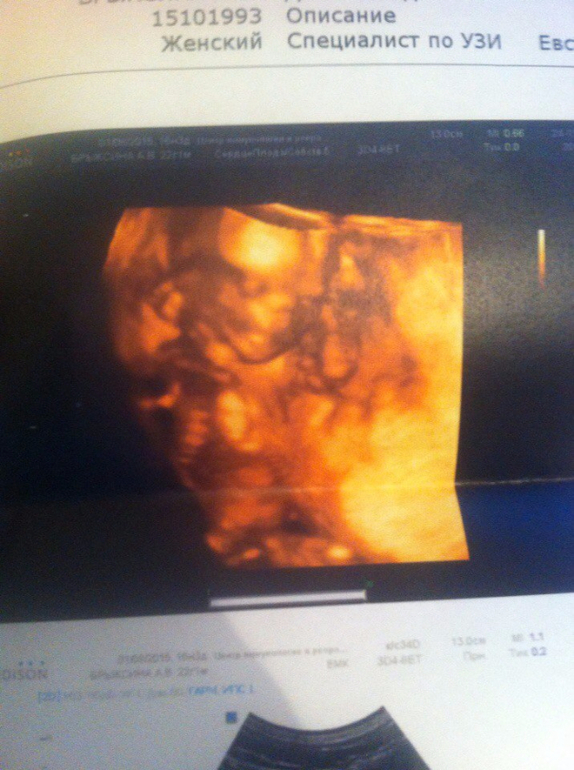

По М срок 16 нед 3 дня, по узи - 15 нед 6 дней, мы и на первом скрининге отставали на 4 дня) Так что ПДР переносится на 11 мая, я рада)))Рост нашей девочки 15 см, а вес - 130 граммов!

Все параметры в норме, кроме одного - нашли "в сосудистом сплетении правого бокового желудочка головного мозга анэхогенные включения размерами 4 мм и 7 мм" - то есть две кисты. Сказали, что не страшно, и скорее всего рассосется... Прошерстила ББ и ИНтернет на эту тему, я так понимаю, что такое бывает, но нет поводов для волнения, т.к. другие показатели все в норме. Но поволноваться нас с мужем эта фраза заставила жутко....

Прикрепление по задней стенке, головное предлежание, плацента (ура!) поднялась!

Малышка вредничала, легла совсем неудобно, хоть я и поела сладкого, поэтому видео записать не вышло, и в 3Д получилась только одно фото, но я рада, в 2д видно лучше, т.к. пока мы ещё маленькие)) Потом малышка повернулась на несколько минут - видимо, для фото))) Модель)))